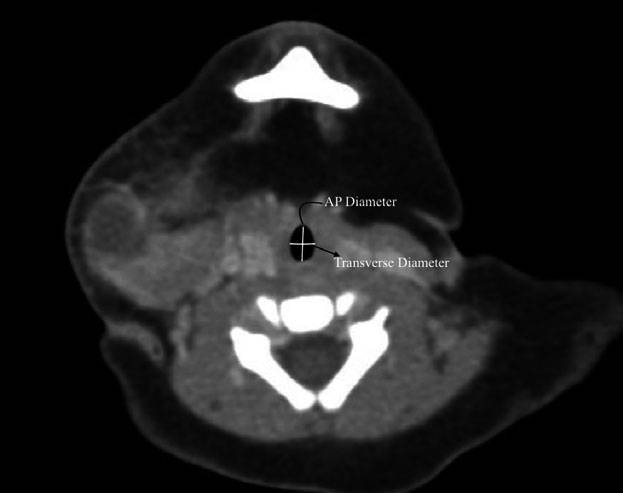

Figure 1 Computed tomography image in the transverse plane of the airway at the subglottis in a 3-month-old girl showing that the anteroposterior diameter is greater than the transverse diameterthereby resulting in an elliptical shape to the airway.

作者在两个水平(声门下和环状软骨环,图1和图2)测量喉部的横径和前后径。由2位作者分别对影像进行测量,并由第3名作者对测量结果进行验证。所有作者在测量时均不知道患儿的年龄。测量结果包括声门下和环状软骨水平气道的横径和前后径。椭圆形或圆形横截面的计算使用公式Area =π (½T × ½AP)。

不同性别或不同年龄(小于6月和大于6月)患者的测量结果没有差异。总体而言,从声门下水平到环状软骨水平其横径的大小是增加的(5.3 ± 0.84 mm vs 6.1 ± 0.86 mm),而前后径却是减少的(7.2 ± 0.87 mm vs 6.7 mm ± 0.75 mm),其差异均具有统计学意义。声门下横径和前后径的比值是0.74,而环状软骨处横径和前后径的比值是0.89。两个水平的横截面积相似,分别是声门下29.9 ± 7.5 mm2和环状软骨水平32.1 ± 7.8 mm2。声门下和环状软骨的测量结果显示前后径均大于横径,因此气道在这两个水平均呈椭圆形(表1)。